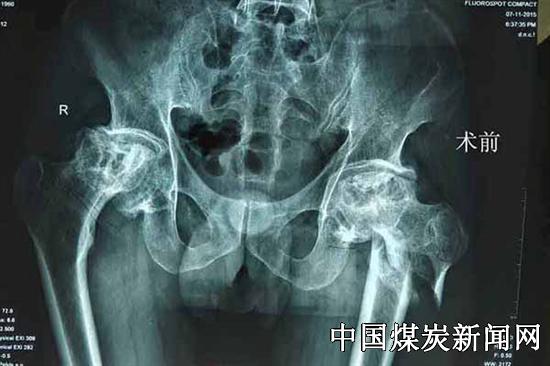

【本网讯】近日,冀中能源峰峰集团总医院邯郸院区成功利用3D打印技术开展了全髋关节置换术,利用3D打印技术辅助全髋关节置换术,在邯郸市尚属首例。目前患者恢复良好,已经出院。此前峰峰集团总医院曾完成3D打印辅助膝关节置换。

一名50多岁的男性武姓患者,因摔伤导致粗隆下粉碎性骨折伴有股骨头坏死10余年,影响该患者生活质量。长期股骨头坏死造成髋臼底骨质菲薄,用普通生物髋臼容易造成术后松动,考虑到患者症状,总医院邯郸院区骨四科主任王晖本科团队经过缜密研究,决定利用高科技3D打印给其私人订制髋关节来准确手术。

3D打印人工髋关节的最大特点在于臼杯,3D打印的臼杯及其微孔表面是一体成型,医生将检查的影像数据传给3D打印部门,工程人员再将数据通过软件分析重建成三维立体,按照设定的形状,把预先放入工作舱中的钛合金粉一层层堆积制造,最终打印成型。骨四科主任王晖采取“骨小梁3D打印髋臼”的技术,改善通用器械对复杂病例的处理局限。通过精确的3d打印技术来保证对患者进行全髋关节置换手术准确操作,患者术后早期就可下地行走。3D打印技术应用在髋关节置换上的应用,可有效解决了髋关节翻修、DDH畸形、粗隆间粉碎性骨折等疑难病症,减轻患者的痛苦,减少假体松动和术后并发症,提高了手术的成功率。